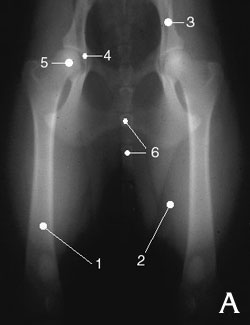

Radiographies des hanches de deux chiens différents

Hanches normales

Légende :

1. Fémur

2. Muscles

3. Bassin

4. Acétabulum (cavité qui reçoit la tête du fémur)

5. Tête du fémur

6. Vertèbres coccygiennes (base de la queue)